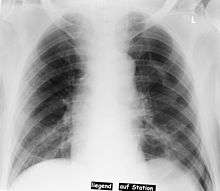

Deep sulcus sign

Pneumothorax left sided

In radiology, the deep sulcus sign on a supine chest radiograph is an indication of a pneumothorax.[1][2] In a supine film (common in the ICU), it may be the only indication of a pneumothorax because air collects anteriorly and basally, within the nondependent portions of the pleural space as opposed to the apex (of the lung) when the patient is upright. The costophrenic angle is abnormally deepened when the pleural air collects laterally, producing the deep sulcus sign. Patients with chronic obstructive pulmonary disease (COPD) may exhibit deepened lateral costophrenic angles due to hyperaeration of the lungs and cause a false deep sulcus sign.